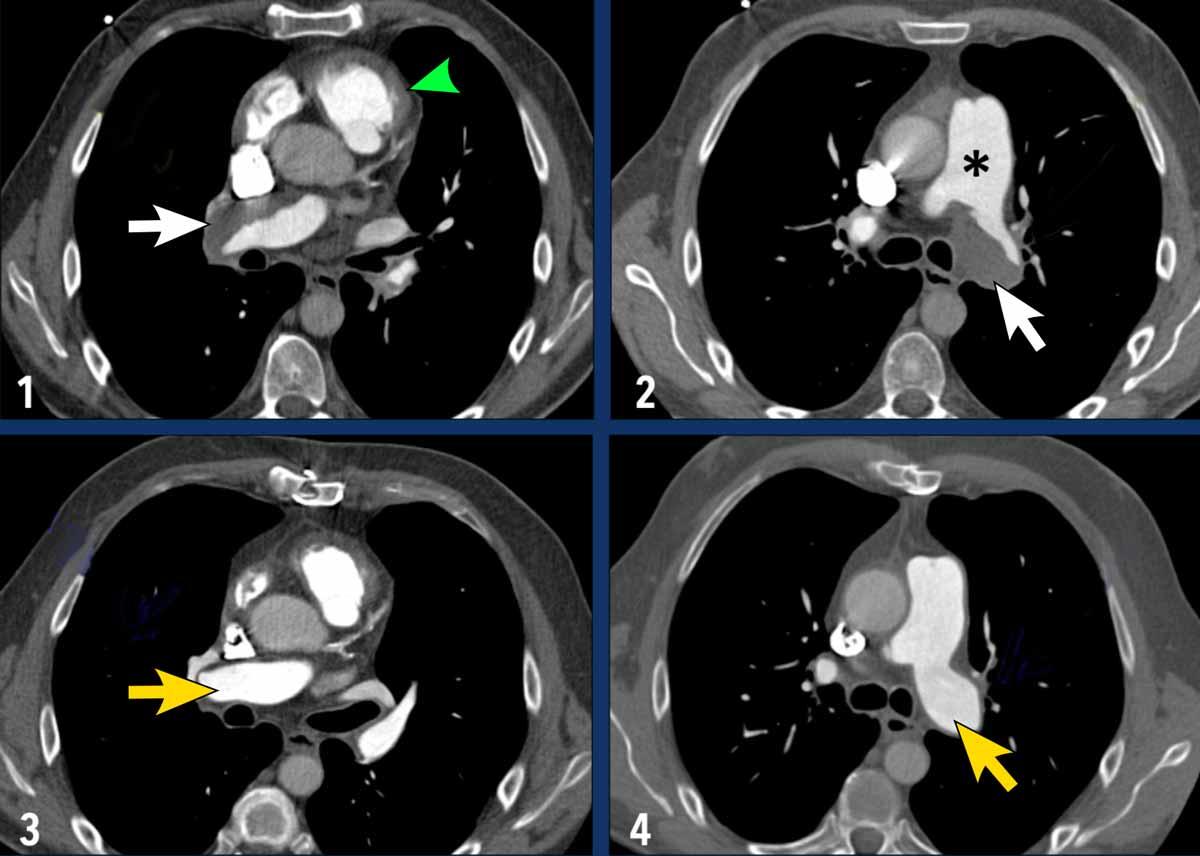

Các hình ảnh này thuộc về bệnh nhân bị CTEPH nặng.

- Giãn nhĩ phải và thất phải kèm phì đại cơ thất phải (mũi tên trắng).

- Dải mô (web) gây hẹp động mạch phổi phân thùy; đây là một trong những đặc điểm của bệnh huyết khối tắc mạch mạn tính (mũi tên xám).

- Hình ảnh chụp mạch phổi cho thấy tắc hoàn toàn (mũi tên đen) và hẹp các động mạch phổi phân thùy, kèm theo các khuyết tưới máu lớn.

- Các khuyết tưới máu hình chêm trên xạ hình tưới máu.

Hình ảnh

- Trước phẫu thuật nội mạc (Hình 1-2): vật liệu huyết khối bám thành mạch được thấy ở cả động mạch phổi phải và trái (mũi tên trắng). Ngoài ra còn có giãn đáng kể thân động mạch phổi chính (dấu hoa thị) và phì đại thành đường ra thất phải (đầu mũi tên xanh lá).

- Sau phẫu thuật nội mạc (Hình 3-4): Các động mạch phổi hai bên đã được làm sạch vật liệu huyết khối.